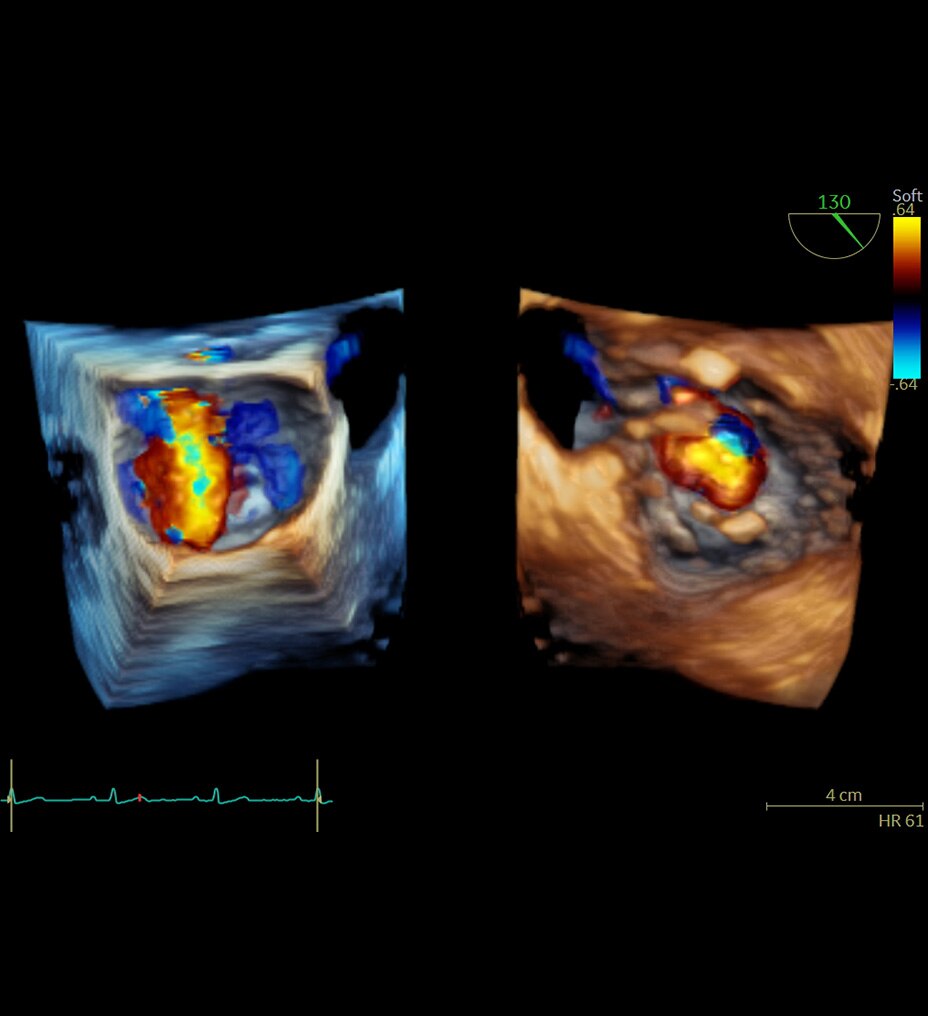

Die Kardio-Bildgebung in nur einem Herzschlag ohne Kompromisse wurde entwickelt, um eine konsistente, qualitativ hochwertige Bildgebung für genaue Diagnosen zu ermöglichen, und zwar selbst bei schwierigen Fällen mit Vorhofflimmern, Problemen beim Atemanhalten, stark verkalkten Herzkranzgefäßen, In-Stent-Restenosen und in Situationen, in denen keine EKG-Kurve verfügbar ist.